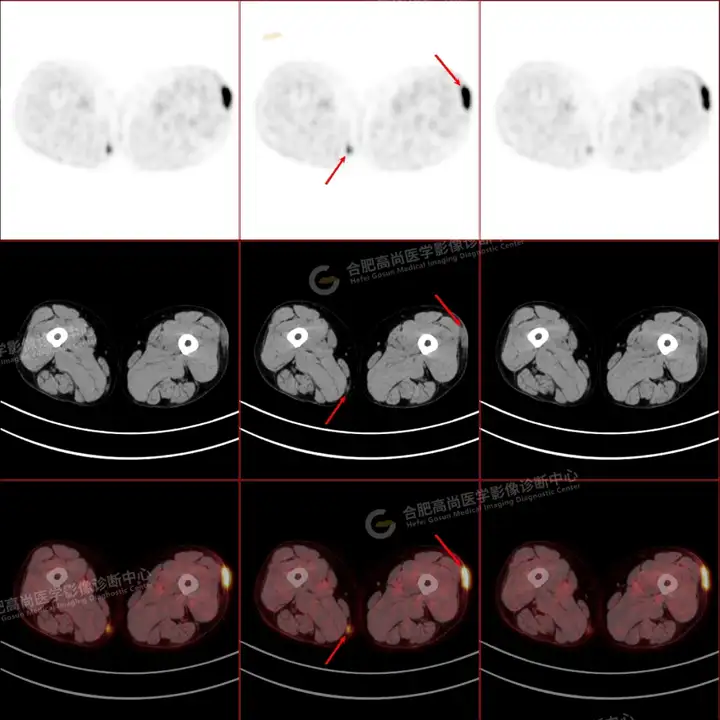

PETCT检查所示:图1、3-17全身多处(双上臂、胸背部、左侧乳腺、左侧腰部、腹壁、双侧臀部及双侧大腿)皮肤下结节及肿块样软组织密度灶,FDG代谢不同程度增高,双侧颈部、左侧锁骨区、纵隔内(1区)及双侧腋窝多发肿大淋巴结,FDG代谢明显增高,符合皮肤来源淋巴瘤。

图2右侧颈部包块切除术后,右侧锁骨区术区皮下片状密度增高灶,FDG代谢异常增高,考虑术后炎性反应。